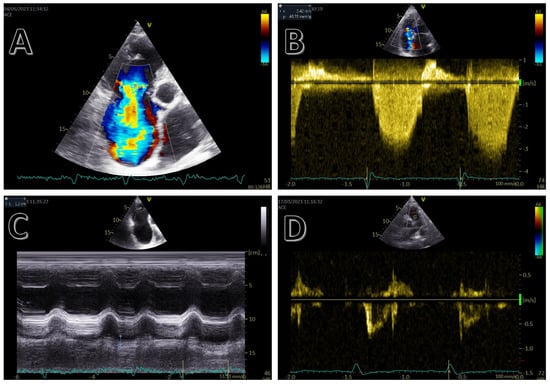

3. Echocardiography